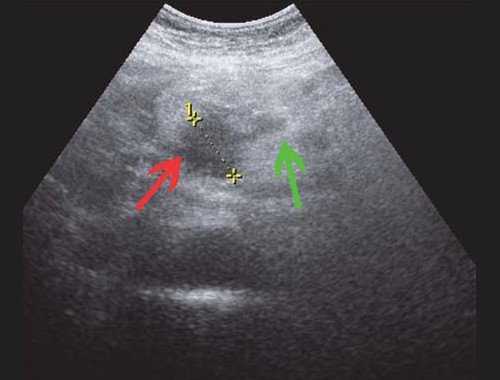

(Левый) На косом трансабдоминальном УЗ срезе в печени определяется умеренное расширение общего желчного протока и ответвляющихся внутрипеченочных протоков; эти изменения вызваны обструкцией протоков опухолью головки поджелудочной железы (не показана).

(Правый) При цветовой допплерографии у того же пациента отмечается отсутствие кровотока в расширенных тубулярных структурах, что указывает на то, что это и в самом деле расширенные желчные протоки. Следует выполнять цветовую допплерографию в повседневной практике для подтверждения дилатации желчных протоков.

Рис. 4. Ультразвуковая картина опухоли головки ПЖ: образование в головке ПЖ (красная стрелка), расширенный панкреатический проток (зеленая стрелка).